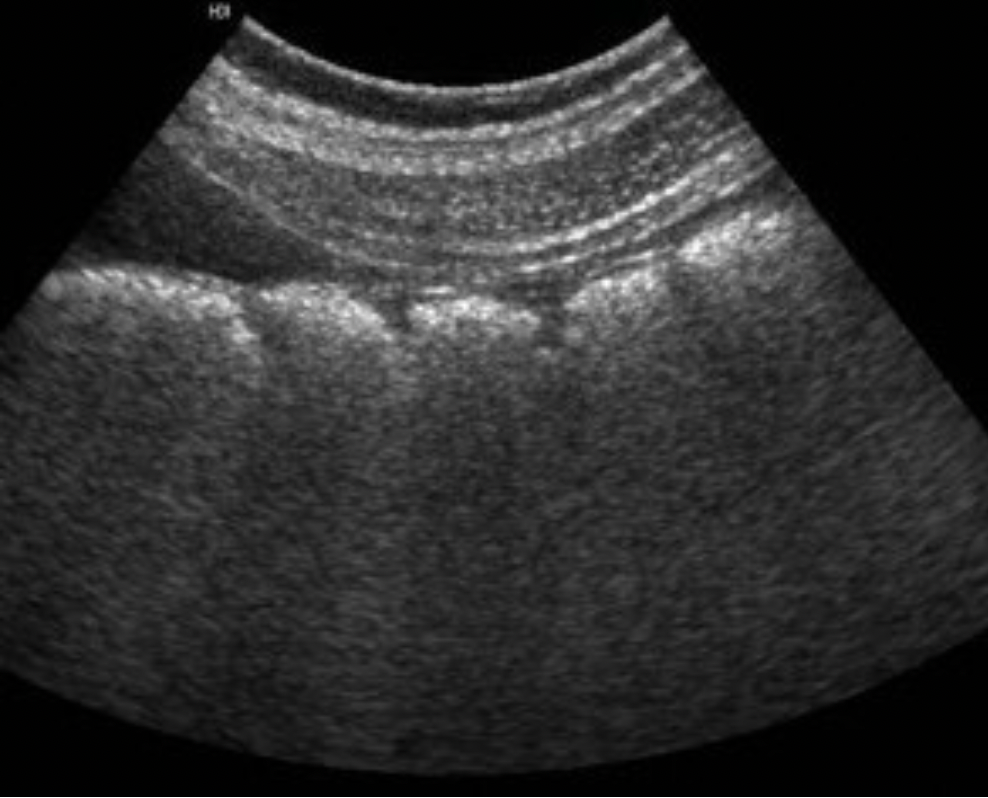

Which blood vessel is located lateral to the left lobe of the thyroid and demonstrates an anechoic ovoid shape in a transverse view of the mid thyroid?

B. left internal jugular vein

The internal jugular vein is located lateral to the left lobe of the thyroid and demonstrates an anechoic ovoid shape in a transverse view of the mid thyroid. The carotid artery is also lateral to the thyroid lobes but it should be a circular structure.

The image displays the left lobe of the thyroid with the circular CCA immediately lateral to the mid lobe and ovoid IJV lateral to the CCA.

Which blood vessel is located lateral to the right lobe of the thyroid and demonstrates an anechoic circular shape in a transverse view of the mid thyroid?

C. right common carotid artery

The right common carotid artery is located lateral to the right lobe of the thyroid and demonstrates an anechoic circular shape in a transverse view of the mid thyroid.